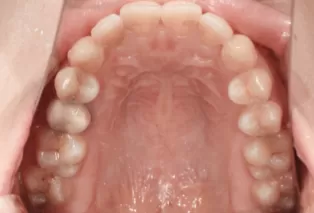

Photos intra-orales